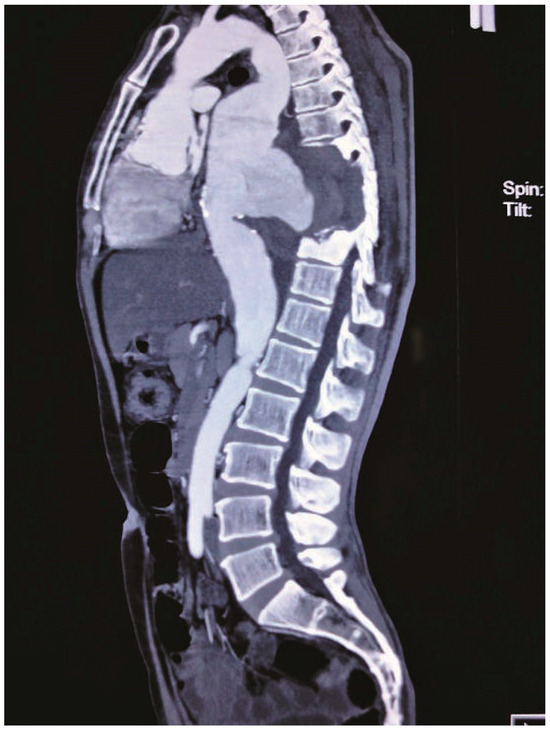

Neo Snowman in X-Ray

Case report